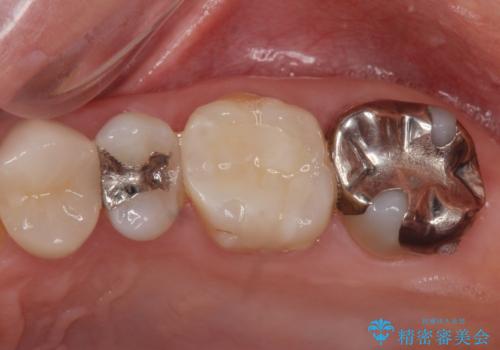

- 矯正前の患者様です。検査により虫歯がありましたのでe-maxインレー治療を行いました。

- e-maxインレー 7.7万×2費用は治療当時の料金となります

虫歯がある状態で矯正を始めてしまうと矯正治療中に虫歯が悪化してしまう可能性があります。